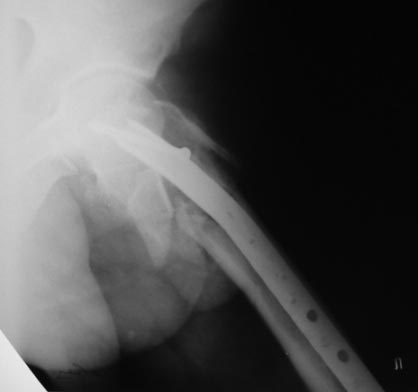

Уважаемые коллеги! На консультацию пришел больной 44-х лет (снимки 1 и 2): упал на улице 26.11.2012г., оперирован в одном из лечебных учреждений 26.11.2012.

Сделали контрольные рентгенограммы и КТ. Хотели-бы обсудить варианты оперативного лечения: DHS или БИОС?